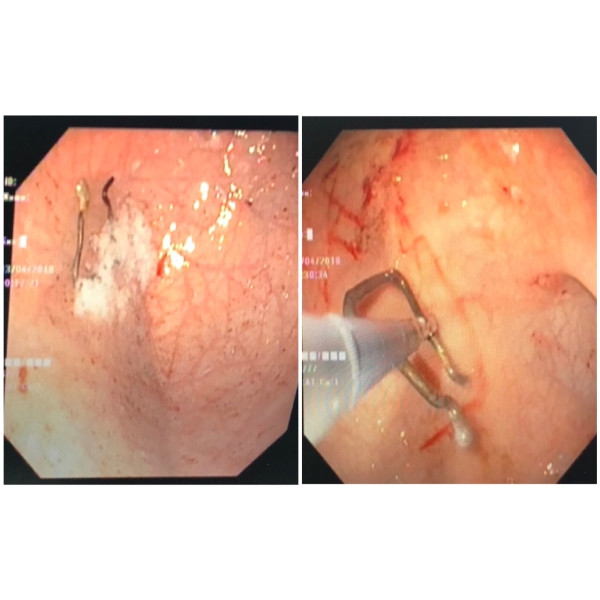

Nuốt móc sắt kẹp quần áo, bé trai 18 tháng suýt thủng ruột ảnh 1Hình ảnh nội soi X-quang cho bệnh nhi. ảnh: BVCC

BS.CK2 Nguyễn Minh Ngọc (Trưởng khoa Tiêu hóa BV Nhi đồng 2) cho biết ngay khi tiếp nhận bệnh nhi,ekip nội soi tiêu hóa nhận định đây là 1 trường hợp khó vì hình dáng dị vật có 2 cạnh sắc nhọn với kích thước lớn, khi gắp dị vật có thể gây tổn thương nhiều ở niêm mạc đường tiêu hóa.

“Chúng tôi xác định cần phải tiến hành lấy dị vật ngay trước khi dị vật này di chuyển sâu hơn, gây biến chứng thủng ruột. Ekip đã nhanh chóng liên lạc và cùng phối hợp với đồng nghiệp nội soi của BV Chợ Rẫy để tiến hành nội soi lấy dị vật ra ngoài”, BS Ngọc cho biết.

Các BS đã tiến hành dùng các dụng cụ có thể che chắn được cạnh sắc nhọn của dị vật, tránh gây trầy xước thêm đường tiêu hóa để phối hợp lấy dị vật ra ngoài.